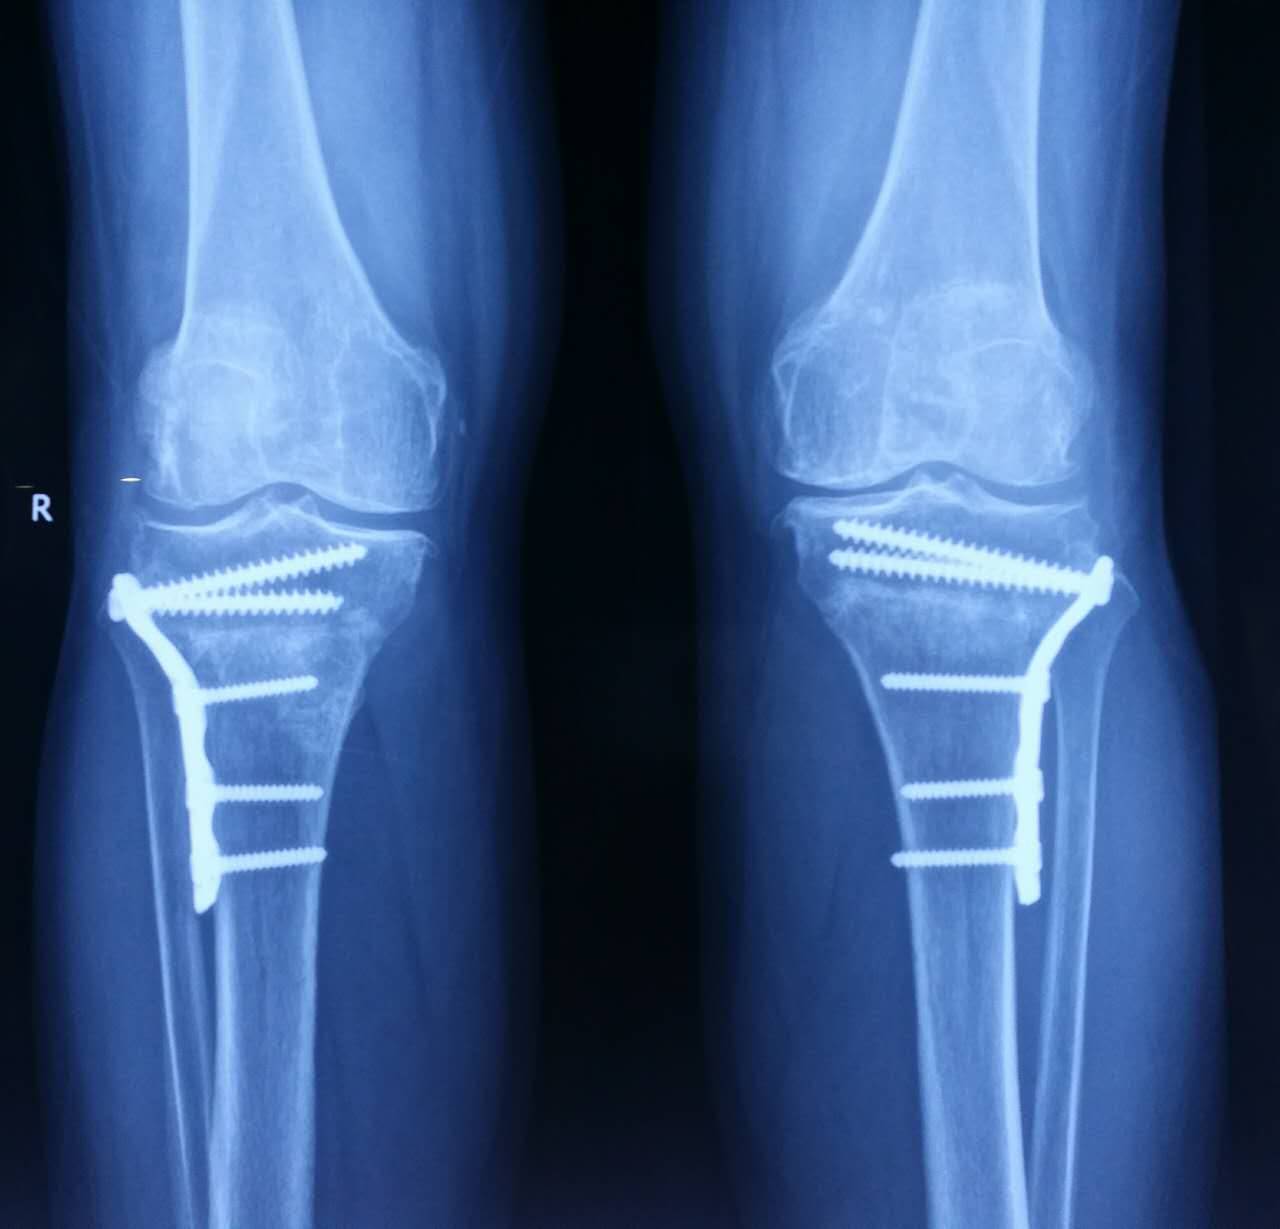

1、外伤骨头——粗看X光片、细看CT

各种外伤,如果怀疑伤到了骨头,优先选择X光照片,检查结果快速易得。若要进一步观察,可以选择CT。超声、核磁对于骨皮髓质等看不大清,一般不选择。

微创手术:发明专利针镰刀结合骨科手术微创治疗狭窄性腱鞘炎,拇外翻,斜颈,小儿脊柱侧弯,腋臭,斑痕挛缩等病变。创新循法针刀,治疗各类疼痛、骨质增生有奇效,并大大提高了安全性,避免了副损伤。以其“用时短、不开刀、不包扎、不住院、费用小”赢得广大患者的信赖和好评。独创股骨头坏死微创减压松解术、骨性关节炎膝内翻V--L截骨术,临床应用效果良好。